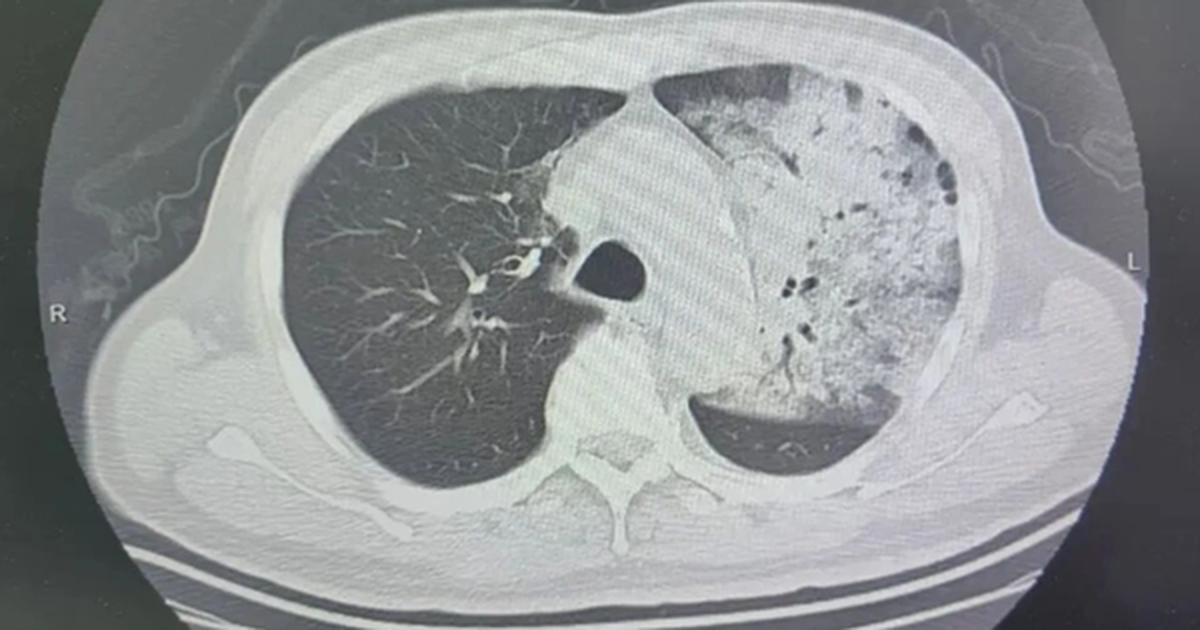

- Bệnh nhân sốt 40 độ C, phổi 'trắng xóa' và suy đa tạng chỉ trong vài ngày [1, 2].

Tình trạng bệnh nhân nguy kịch